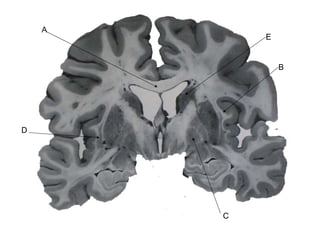

E B C D A

Answer Key A: corpus callosum B: extreme capsule C: globus pallidus D: claustrum E: caudate nucleus

E B CD A

Answer Key A:corpus callosum B: extreme capsule C: globus pallidus D: claustrum E: caudate nucleus